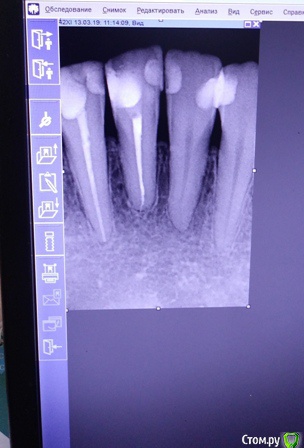

Есть рецессии на нижних зубах и на верхнем клыке слева и резорбция. Ортодонты говорят, что это последствия неправильного прикуса, травмирующего смыкания и с брекетами все стабилизируется, но из-за движения зубов может и усугубиться, как повезет. Вестибулопластику никто не предлагал, а один вообще сказал, что в моем случае она бесполезна. У хирурга-парадонтолога другое мнение: нужно сделать сначала операцию на нижних зубах (углубить преддверие, устранить тяжи и положить какой-то там замещающий материал), а потом поставить брекеты, иначе без операции брекеты спровоцируют еще большее оголение и рецессии станут просто огромными.  А после брекетов уже закрывать, если нужно, рецессии.  Прошу поделиться вашим мнением? В чем причина рецессий и резорбции? Поможет ли в моем случае вестибулопластика?